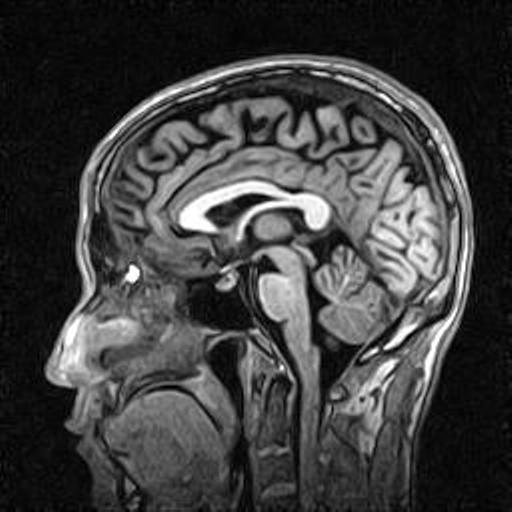

3D GE IR option enables volumetric scanning with high resolution and excellent white-grey matter contrast.